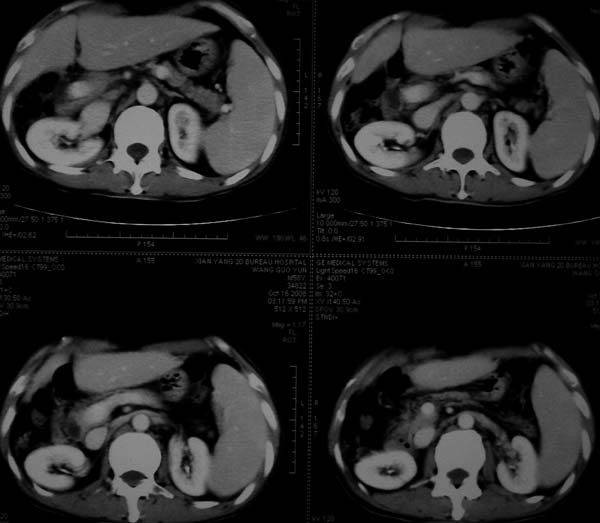

标题: CT16292:男,53岁,上腹部不适2月,B超发现肝内占位病变。 [打印本页]

标题: CT16292:男,53岁,上腹部不适2月,B超发现肝内占位病变。

符合肝ca增强,\"快进快出\";肝叶比例失常,右叶萎缩,肝裂增宽,脾大,肝硬化可能.

支持结节型肝癌。肝硬化脾大,病人是不是做过手术。

肝脏体积变小,肝裂增宽,分布异常,肝尾叶增大,脾肿大,考虑肝硬化可能性大,右肝病灶呈现早期充盈,延迟强化考虑肝内胆管细胞癌可能,不除外血管瘤

肝硬、脾大,右肾在稍息,考虑结节型肝癌可能,不排除血管瘤。

支持 结节型肝癌;肝硬化、脾大。

肝硬化,多结节肝癌。比较典型的表现了。

肝叶比例失调,左叶增大,肝裂增宽,脾脏增大,门脉增宽,肝右叶包膜下多发结节样阴影,增强虽说强化幅度不大,但还是符合快进快出特点;考虑肝硬化、脾大、结节型肝癌。胆管细胞癌多有延时强化、肝包膜凹陷征、周围胆管扩张等特点,本例明显不符;故不考虑。

支持结节型肝癌 肝硬化 脾大